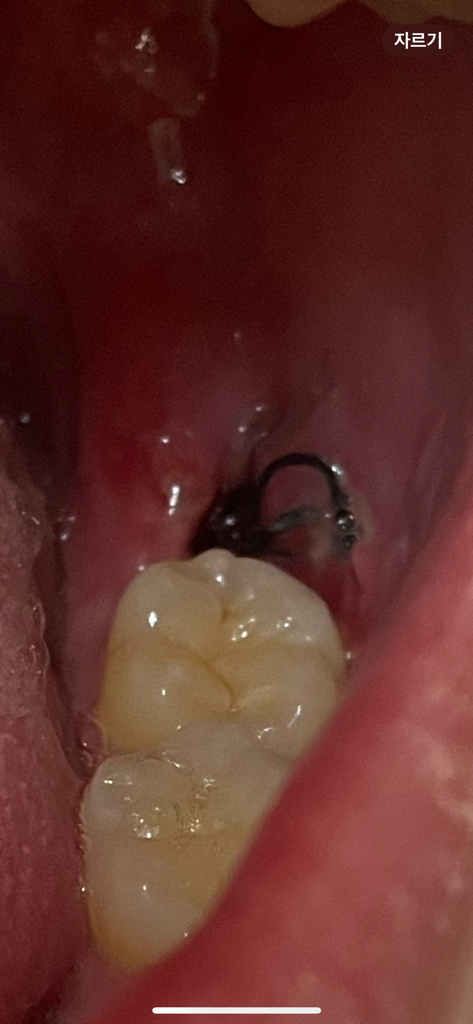

사랑니 발치 후 5일찬데 구멍이 갑자기 생겼어요

원래 안보였는데 오늘 아침에 일어나보니 구멍이 크게 보여서 병원에 내원해야하는지 궁금합니다.

구멍이 크고 되게 깊은 것 같아요

통증은 거의 없습니다.

• 1번 째 사진